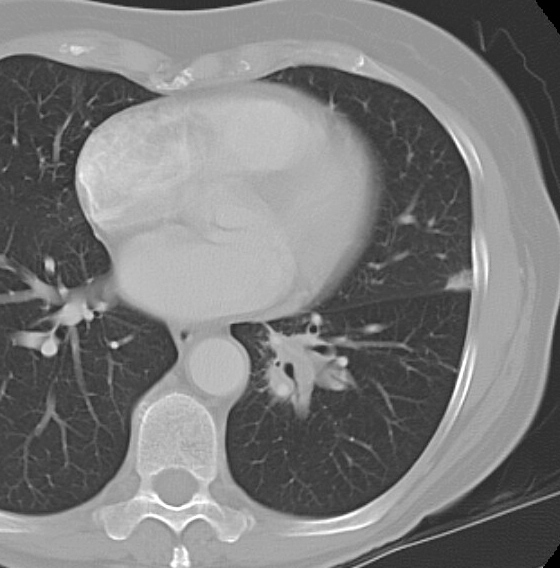

Gallery Mediastinum Lymphoma 8c

8c